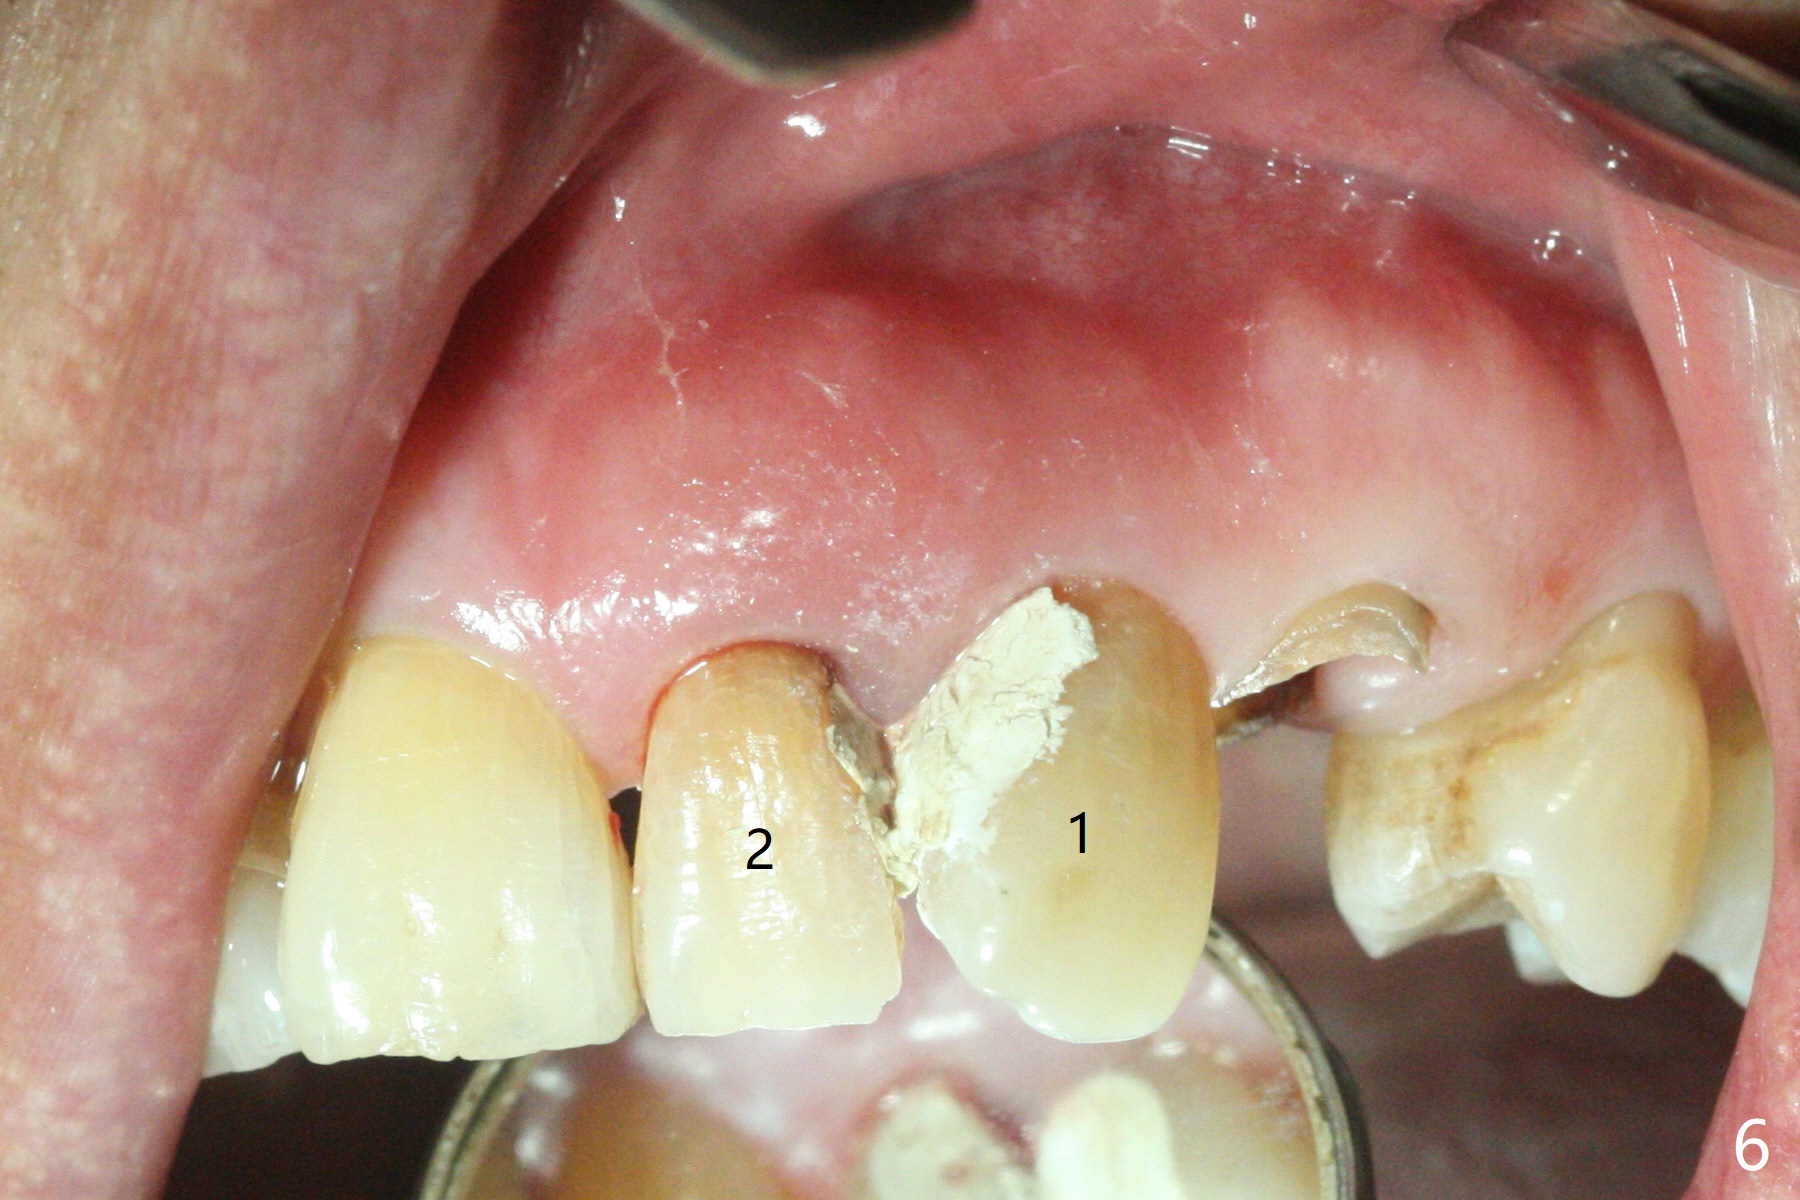

64岁男要求拔除左上3(图一,二),将使用Piezo P3 tip(图三)松动牙根,可行?其实图三是G6,used for removal of calculus from a wide plane. G:可能代表general use or general dentistry,而P牙周(图四)。P3(买了好久,不知道用处)特别细长,容易进入牙周膜,但愿在小功率的普通Piezo Scaler (超声洁牙机)作用下,P3能切断牙周膜,午饭后尝试。其实尖牙无症状(图五),中切牙(在侧切牙位置上)因近中深龋造成牙龈炎症,在病人要求下,清除龋坏后,填入临时充填物(图五,六)。